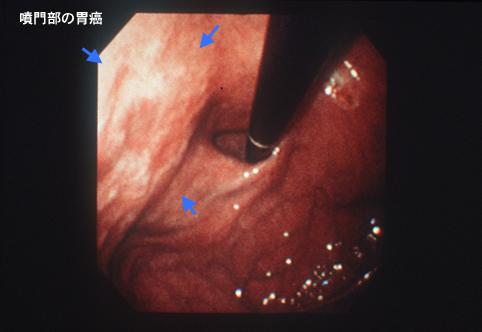

질환(병리주체)의 분류 악성 상피성종양/편평상피암

부위(장기별) 위(부위)/궁륭

검사방법 내시경

종양의 육안분류 0형(표재형)/IIc형(IIc)

종양의 최대경(밀리미터) 1~9

종양의 심달도 m

다발종양(동일 장기) 유(동시성)

다중종양(다수의 장기) 유(동시성)